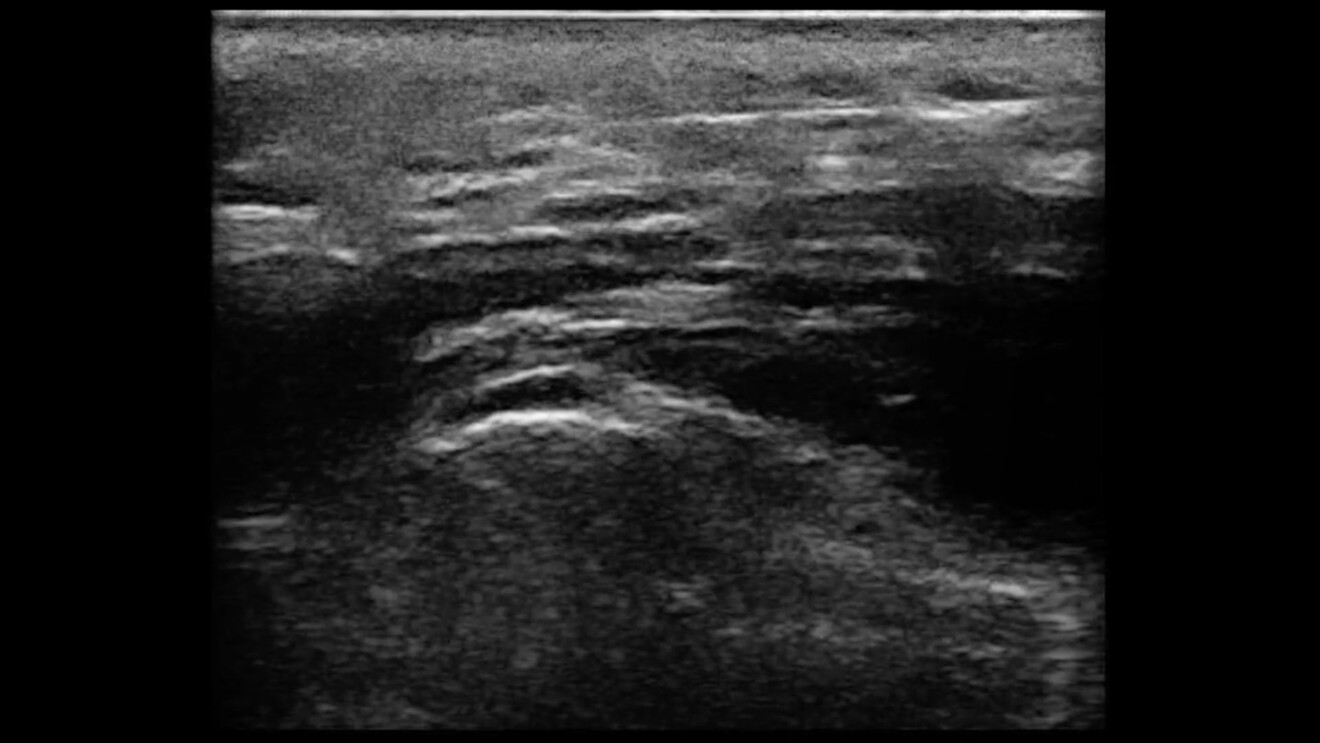

• Monitorare l’accesso, il posizionamento e la prosecuzione dello strumento nel contesto tissutale desiderato: il tessuto adiposo superficiale si presenta come uno strato tissutale ipoecogeno a lobuli determinati da molteplici sottilissimi setti fibrosi iperecogeni che li contornano. Lo strumento – evidenziato dalla funzione di magnificazione dell’ago – è una linea iperecogena che conferma la wellpractice dell’operatore o distingue un errore iatrogeno.

• Delimitare il tessuto da non superare o da raggiungere: lo SMAS si presenta come uno strato iperecogeno a struttura che varia da uniforme a frammentato, il tessuto muscolare dei muscoli mimici del volto, ipoecogeno a strie iperecogene… sono nello stesso tempo limiti per alcune procedure infiltrative e implantari mentre sono obiettivi da raggiungere e da non superare nelle procedure di iniezione intramuscolare della tossina botulinica. Gli spazi facciali quasi sempre ipoecogeni – laddove esistenti – e il tessuto osseo, curvilineo, iperecogeno, divengono aree ove infiltrare il filler in sicurezza evitando anche indesiderate migrazioni.

• La metodica intramuscolare: Questa metodica iniettiva, propria della tossina botulinica, prevede che l’ago penetri il muscolo mimico del volto con un’angolazione prevista fino a raggiungere la sua parte più attiva. Per questo si preferisce iniettare il muscolo alla massima contrazione. Questo accorgimento dinamico, a causa della sottigliezza dei muscoli facciali (alcuni come il nasalis, meno di 2 mm a riposo e intorno a 3 mm in massima contrazione, oppure il m. frontalis ca 3 mm a riposo e in alcuni punti anche in massima contrazione, il m. procerus fra i più spessi, misura 1,5-3 mm a riposo e in massima contrazione non supera i 5 mm), spesso non è sufficiente. Si rende pertanto indispensabile una guida ecografica in B mode con la funzione di magnificazione dell’ago.